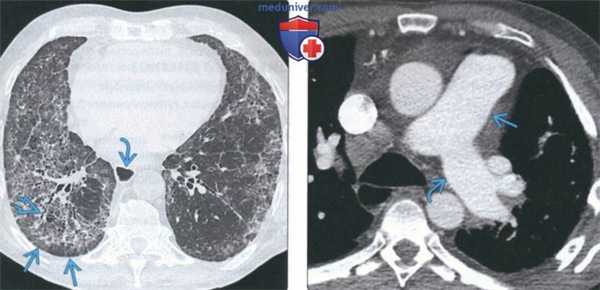

(Слева) На аксиальной КТВР у пациента с прогрессирующим системным склерозом и НСИП определяются двухсторонние участки «матового стекла» и ретикулярные изменения в сочетании с тракционными бронхиолоэктазами. Субплевральные отделы легких интактны, что характерно для НСИП. Обратите внимание на расширение пищевода.

(Справа) На аксиальной КТ с КУ у пациента с прогрессирующим системным склерозом и интерстициальным заболеванием легких определяется расширение легочного ствола и левой легочной артерии, обусловленное легочной гипертензией.